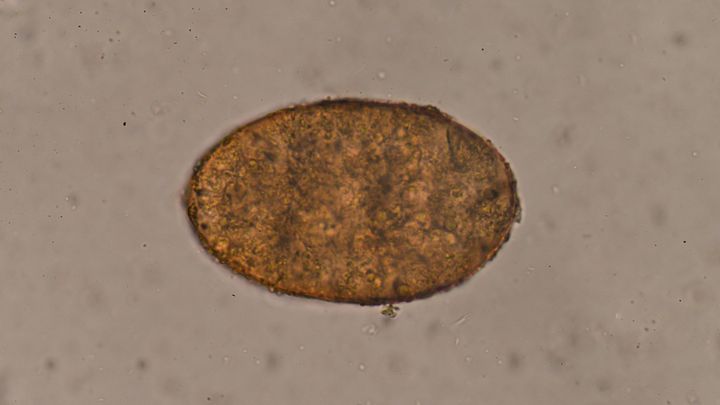

アメリカのカリフォルニア大学デービス校(UC Davis)で行われた研究によって、赤痢アメーバが「他人の皮膚をまとって免疫の目を欺く」驚異のメカニズムと、それを下支えする異常なゲノム構造・RNA干渉ネットワークの全貌が捉えられました。

赤痢アメーバと言えば、多くの人がお腹を壊す「赤痢の原因」という程度の認識しか持たないかもしれませんが、このアメーバには先に述べたような人間の細胞を模倣する恐ろしい擬態能力があるのです。

赤痢アメーバは、古くから赤痢の原因として知られるだけでなく、人間の免疫を巧みにすり抜ける性質がある寄生虫としても注目されてきました。

近年の観察によって、赤痢アメーバがヒトの細胞を“かじり取る”ように破壊する動きを見せることが分かってきました。

一部の研究者たちは、この微生物を「スキンウォーカー(Skin-walker)」と呼ぶほど巧妙な免疫回避能力があると指摘しています。

このかじり取りによって、寄生虫の外面が“ヒト由来”の分子に覆われるため、本来ならすぐに攻撃されるはずの寄生虫が免疫に発見されにくくなるのではないかと考えられています。